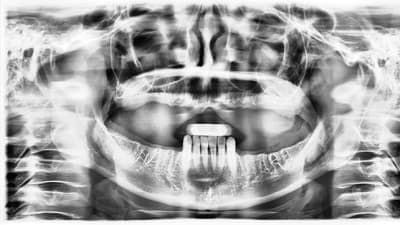

Prosthodontics Prosthodontics Implant-Retained, Solid Zirconia Full Arch Reconstruction By Timothy Kosinski, DDS May 01, 2019 12 min read